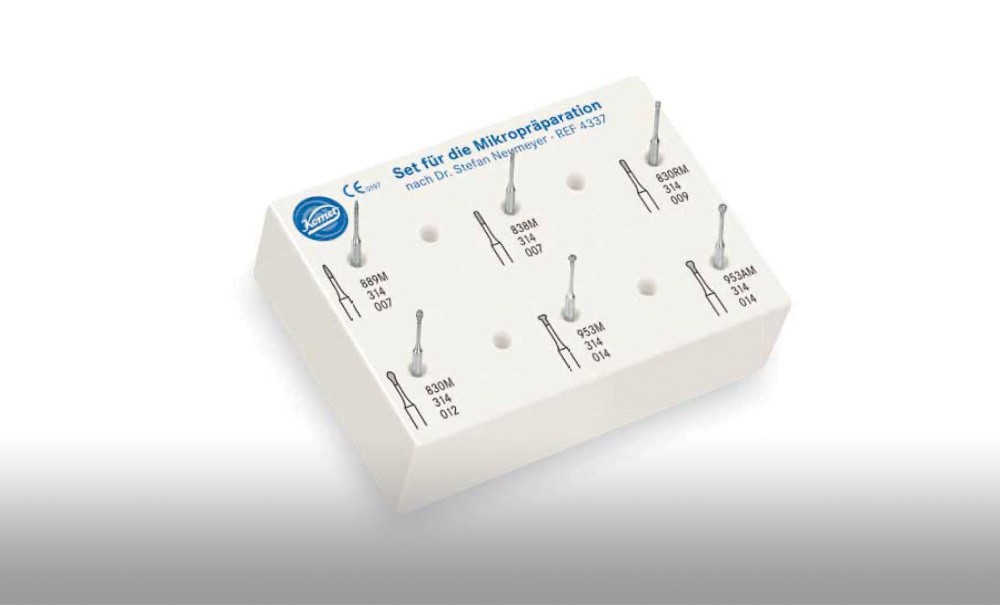

Le chirurgien-dentiste, conscient de l’importance de la préservation des tissus durs de la dent (émail et dentine), de la préservation de la vitalité pulpaire et au fait d’une dentisterie a minima doit tout d’abord établir un diagnostic précoce des lésions carieuses. Ce diagnostic une fois établi, il doit pouvoir disposer d’instruments adaptés à une préservation maximale des tissus dentaires.

- soit de façon invasive a minima. Cette économie tissulaire peut se faire notamment avec l’utilisation de fraises adaptées et minimalement invasives (fig. 4).

• Traitement invasif a minima : il concerne les lésions carieuses cavitaires ou non avec atteinte dentinaire (à partir du 1/3 moyen dentinaire), soit ICDAS 3 à 6. Dans ce cas, la priorité est de préserver la dent d’une effraction pulpaire éventuelle (recommandations de l’ESE) [4]. C’est pourquoi, lors du traitement de lésions carieuses profondes (ICDAS 4 à 6), il faut dans tous les cas réaliser une éviction sélective, réaliser une préparation a minima (favoriser les préparations de type fente (« slot ») ou tunnel lorsque l’indication se pose) et utiliser un matériau de restauration de choix, soit composite, soit un ciment verre ionomère (CVI), soit des matériaux à base de silicate de calcium ou encore les nouveaux composites enrichis en minéraux (fig. 7 à 9). Ces préparations a minima peuvent être réalisées avec des fraises de petits diamètres (fig. 10 et 11).